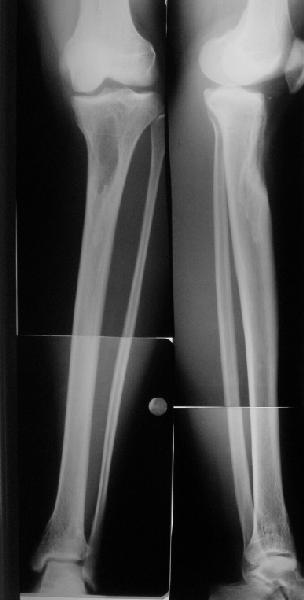

Продолжение обсуждения, начатого в октябре прошлого года (см. здесь) Наконец-то оперировали эту пациентку. Биопсию сделали - опухолевого ничего нет. Пока все участвовавшие в обследовании смежные специалисты и ортопеды сошлись, что это молокальная монооссальная фиброзная дисплазия. 20 марта наложили аппарат, сделали чрескожную остеотомию. К 3 апреля все докрутили. Сегодня заштифтовали. Начальные и итоговые снимки в приложении. Рекурвацию можно было еще немного больше устранить, и чуть кзади сместить диафиз. Но вроде и так ничего выглядит, по сравнению с тем, что было. Комментарии приветствуются.

Александр, по моему великолепно. Поздравлять будем, когда продемонстрируете консолидацию,функцию и внешний вид.

Вопрос: почему дистально только один винт? Предполагаете ли динамизацию?

АС> Вопрос: почему дистально только один винт?

Второй тут можно было сделать динамический, но отломок очень уж длинный, и ротационной подвижности даже без винтов не будет.

Есть клиновидный диастаз, контакт основных отломков на очень небольшой площади только в задненаружном отделе. Так что там скорее межотломковая дистракция, а не компрессия.